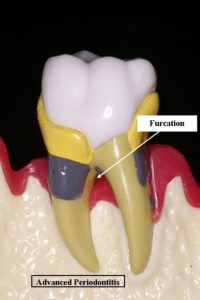

A destructive infection of the gum and underlying bone. It is gingivitis that has gotten out of control and has started to destroy the connection between the gum and the tooth. It is characterized by red, swollen and bleeding gums and will result in tooth loss if it is not treated. The infection causes the bone and ligament which hold the tooth in place to be destroyed. It is also known as periodontal disease and Pyorrhea. How aggressively the infection destroys the bone and gum which support the teeth is influenced by whether or not the patient smokes, if they are diabetic, if they are genetically predisposed, if they are on certain medications and if they clench and grind their teeth. Gum infection has also been linked to cardiovascular disease, stroke, low birth weight and preterm newborns, difficulty in controlling diabetes and recent evidence suggests it may affect Alzheimer’s and upper respiratory tract infections.